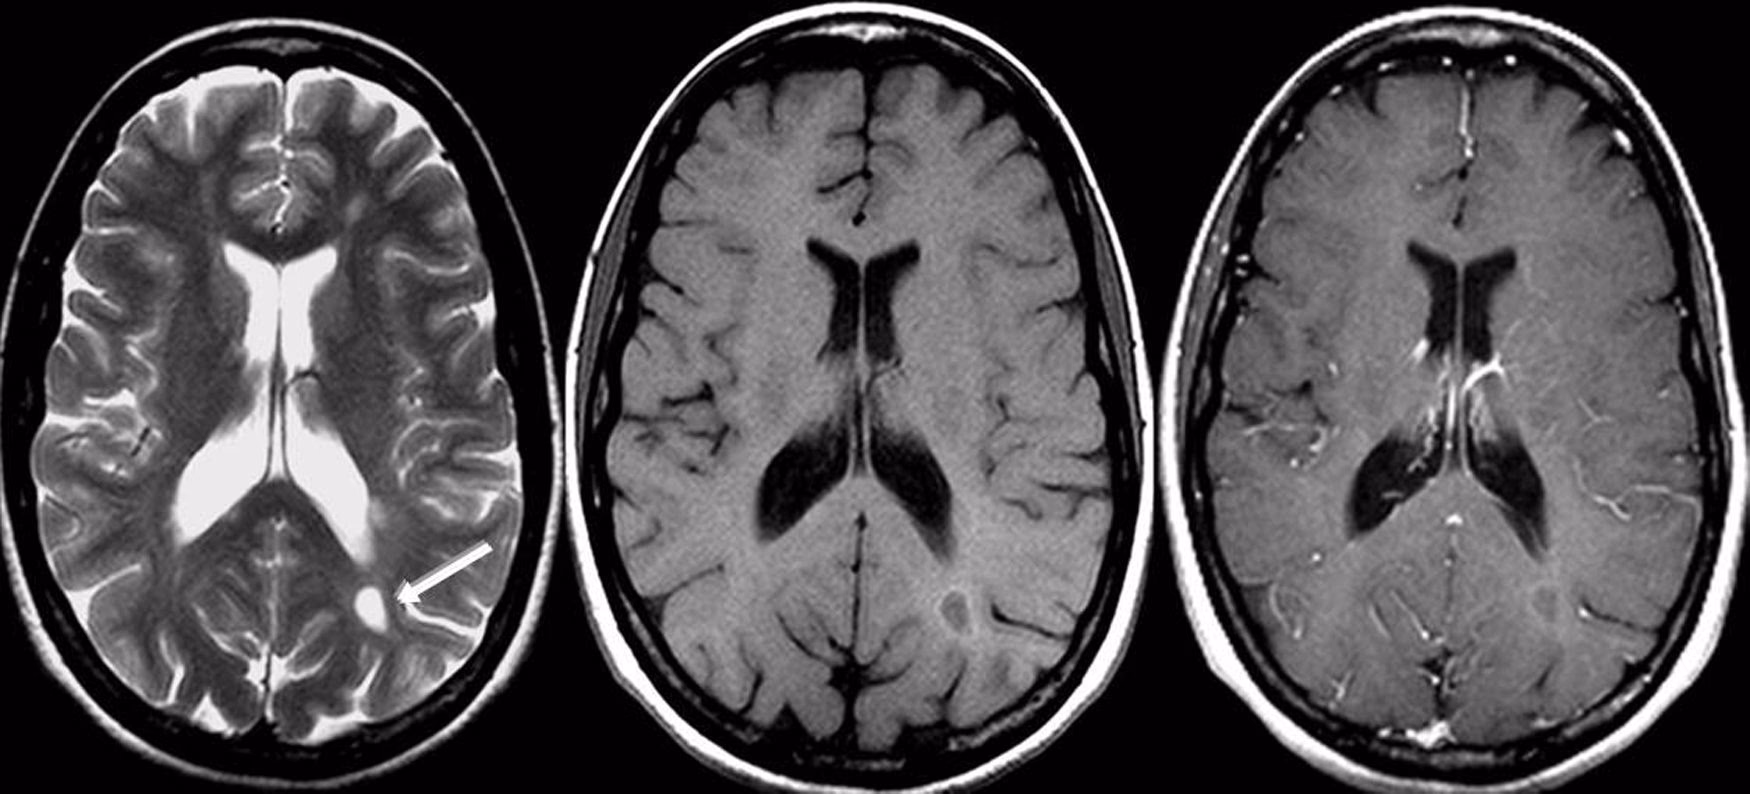

El diagnóstico de una lesión cerebral comienza con una evaluación clínica detallada, que incluye la historia del incidente, un examen físico y una evaluación neurológica para buscar signos de disfunción. Las pruebas de imagen son herramientas esenciales para visualizar el cerebro y detectar el daño.

- Tomografía Computarizada (TC): Útil para identificar rápidamente hemorragias, fracturas de cráneo y contusiones grandes, especialmente en situaciones de emergencia.

- Resonancia Magnética (RM): Ofrece imágenes más detalladas del tejido cerebral y es mejor para detectar lesiones más sutiles como la lesión axonal difusa, contusiones pequeñas o daño isquémico.

Estas herramientas, combinadas con la observación de los síntomas, permiten a los profesionales de la salud determinar el tipo, la ubicación y la gravedad de la lesión.